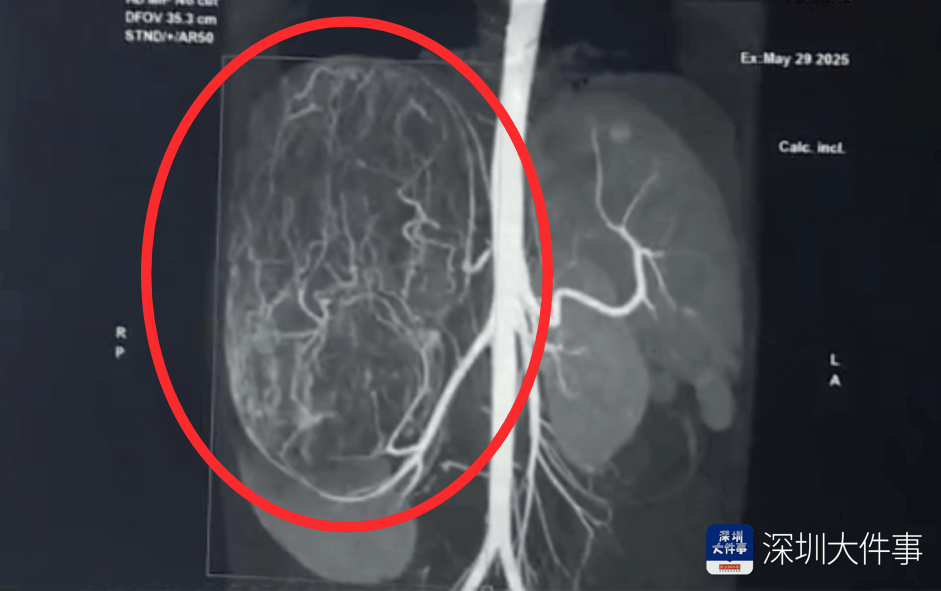

影像检查结果出来,所有人都倒吸一口冷气:一个直径27厘米(比篮球还大)的巨型肿瘤,霸占了整个腹腔右半边王祖蓝。肝脏被它硬生生挤到了肚脐眼以下的位置!

肿瘤体积过大,这也意味着留给医生的手术空间实在有限,强行微创?万一瘤子破了,肿瘤扩散大出血,后果不堪设想!所以,只能通过开放手术来做王祖蓝。

5月30日,医生为婷婷做手术,打开腹腔后,医生遇到了挑战:婷婷的肾动脉异于常人:正常人就1根肾动脉供血,她居然有3根王祖蓝。还有一支来自腹腔干动脉,一支来自腰动脉。

这三根“命脉”就盘踞在巨大的瘤体上,稍有不慎,剪错一根,就可能引发大出血王祖蓝。

手术团队屏气凝神,抽丝剥茧,一根一根精准找到、小心分离、稳稳阻断……经过3个多小时的精密操作:重达2.43公斤直径达27厘米的“巨无霸”肿瘤被完整端出王祖蓝。周围需要清扫的淋巴和脂肪组织也被清除。